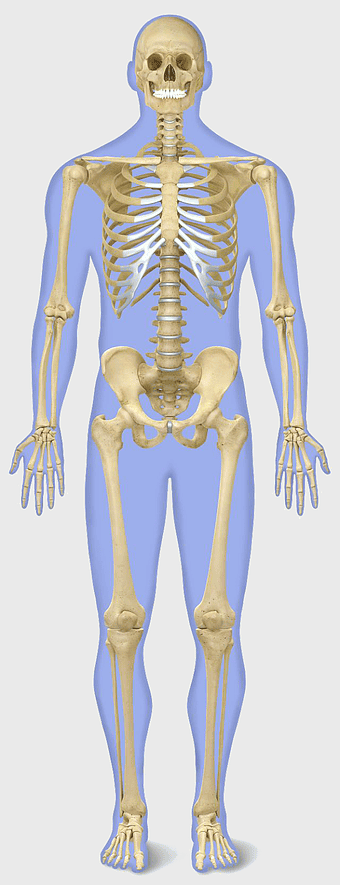

human skeleton illustration, human anatomy bones, skeletal system diagram, human body structure, anatomical reference, medical illustration, educational skeleton image -

2000x4678px

Human skeleton, human body anatomy, standing skeleton, bone structure, skeletal system, medical illustration, human anatomy study -

1250x2083px